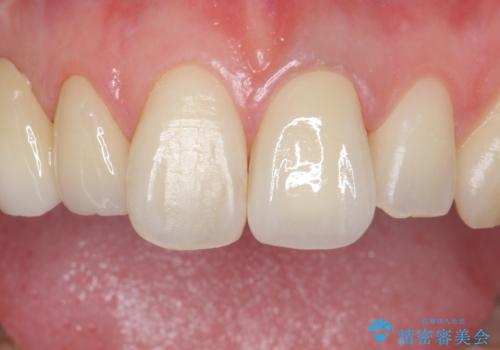

前歯を綺麗にしたい ジルコニアクラウンでの治療

歯ぐきの状態も良く、適合の良い被せ物を入れることができました。

審美性もかなり改善され、大変喜んでいただけました。